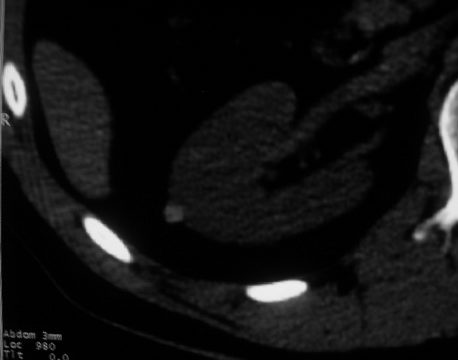

男,体查发现右肝低密度,右肾高密度结节影。高密度ct值92hu,囊肿?

肝右叶囊肿或血管瘤?右肾高密度囊肿。建议增强。

肝右叶圆形低密度灶,考虑囊肿或血管瘤,建议ct增强检查;右肾包膜下高密度圆形灶,考虑:囊肿并出血

考虑肝右叶囊肿,右肾高密度囊肿;建议行ct增强扫描检查。